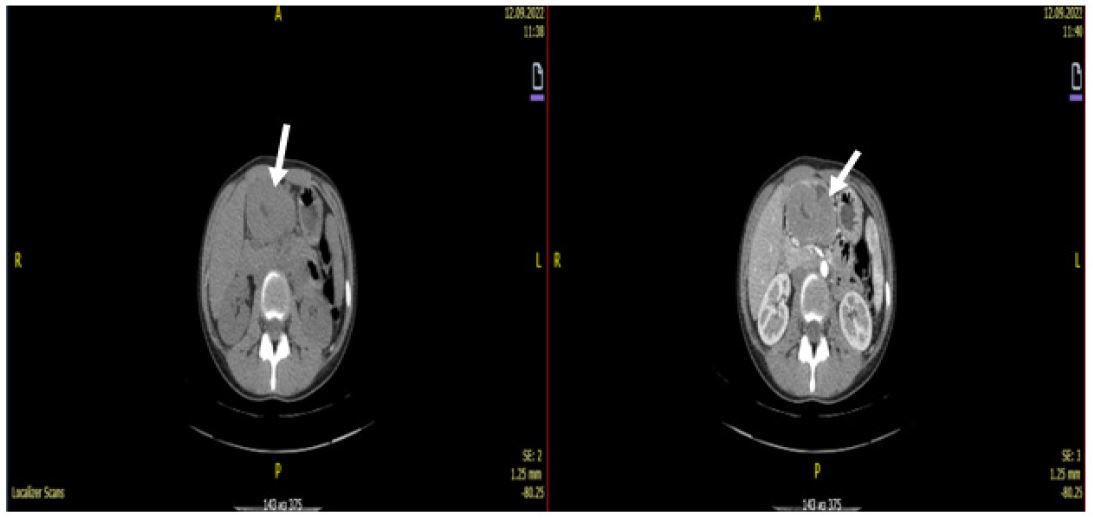

Computed tomography of the abdominal cavity revealed a tumour of the angle and outlet of the stomach (most likely lymphoma), with infiltration of the perigastric tissue (Figures 1,2).

Figure 1: Tumors of the angle and antrum of the stomach with clear contours.

Figure 2: Tumor of homogeneous structure, without signs of invasion into neighboring organs and lymphadenopathy. Diffuse circular thickening of the walls of the antrum of the stomach is noted.